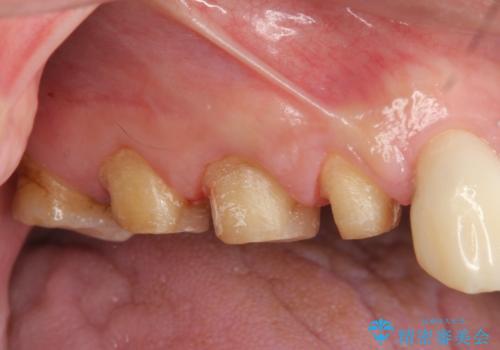

歯周外科で達成する安定したクラウン周囲の歯肉環境

- 重度の歯ぎしり癖で歯がすり減り、見た目・噛み合わせの改善とこれ以上すり減る前の処置を希望され来院されました。

高さが短くなってしまった歯は、安定したクラウンを作るのが難しいため歯ぐきを下げる歯周外科を行ったのちに強度に優れるフルジルコニアクラウンで補綴治療を行います。

すり減ってしまった歯に対し、歯冠長延長術(歯周外科)を行うことで安定したクラウンを製作・装着することが出来ました。